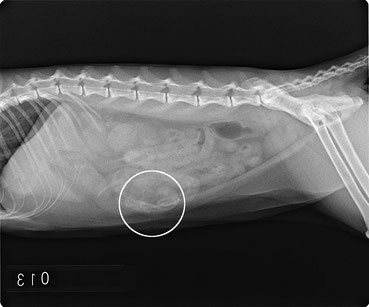

単純撮影のレントゲン写真です。

円の中にうっすら浮かぶ怪しい影がわかるでしょうか?